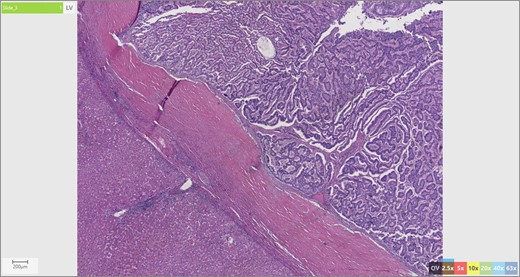

Initial radiographic evaluation with computed tomography (CT) demonstrated a mass in the dome of the liver (Fig. 1a and b). A multiphase magnetic resonance (MR) scan of the abdomen followed and a 3.7 × 5 × 2 cm3 complex lesion was found, containing: cystic elements, macroscopic fat and a calcification (Fig. 1c and d). Percutaneous CT-guided biopsy was then performed and pathology showed atypical columnar epithelium with neuroendocrine differentiation. Both an upper and lower endoscopy did not identify any primary tumor. A positron emission tomography scan did not show evidence of metastatic disease or evidence of other pathology.

(a and b) CT abdomen and pelvis without IV contrast demonstrating tumor in axial (a) and coronal views (b). (c and b). MR abdomen and pelvis with and without IV contrast (Eovist, gadoxetate disodium, Bayer Pharmaceuticals) showing 3.7 × 5 × 2 cm3 complex lesion containing cystic elements, macroscopic fat and calcification in axial (c) and coronal (d) views.